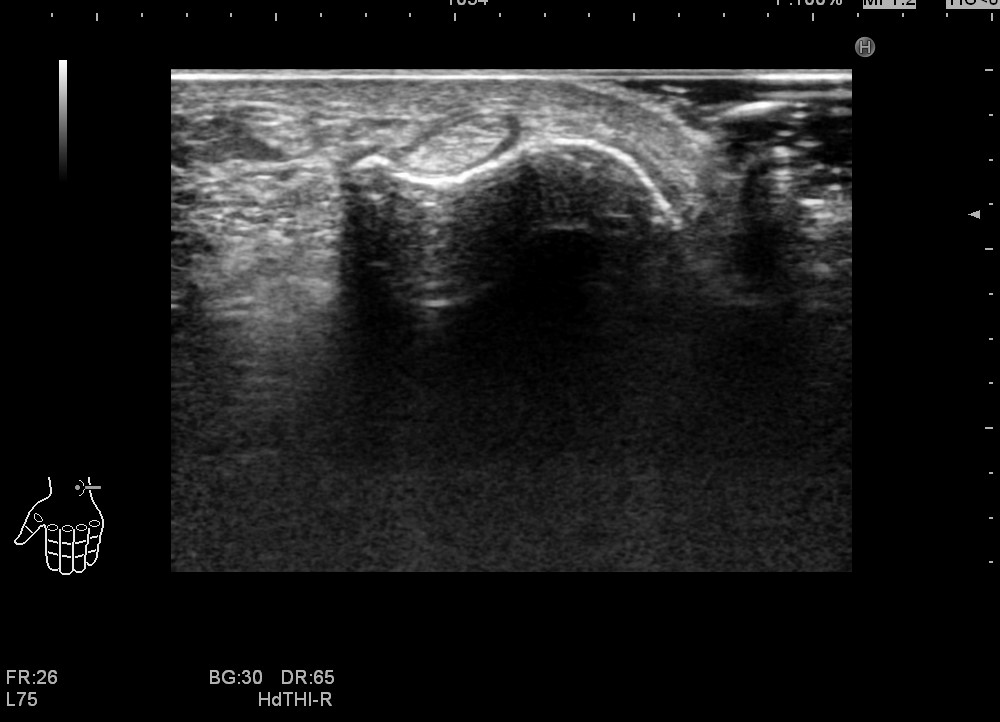

そこでエコーを使いますと実は簡単に場所が確認できます。

四角で囲ったところが尺側手根伸筋腱です。この方は水腫を伴っています。

他の方も

同じようにみえます。脱臼したりしていなければ同定は簡単